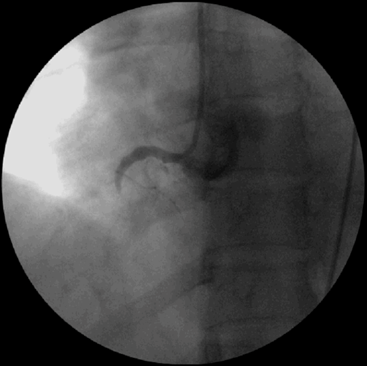

Kết quả chụp động mạch vành: động mạch vành phải tắc hoàn toàn, động mạch liên thất trước hẹp 50%, động mạch mũ hẹp 50%.

Bệnh nhân được đặt stent cấp cứu với thời gian cửa-dây dẫn trong vòng 30 phút với kích thước 4.0 x 28mm, kiểm tra động mạch thông tốt, dòng chảy TIMI3: